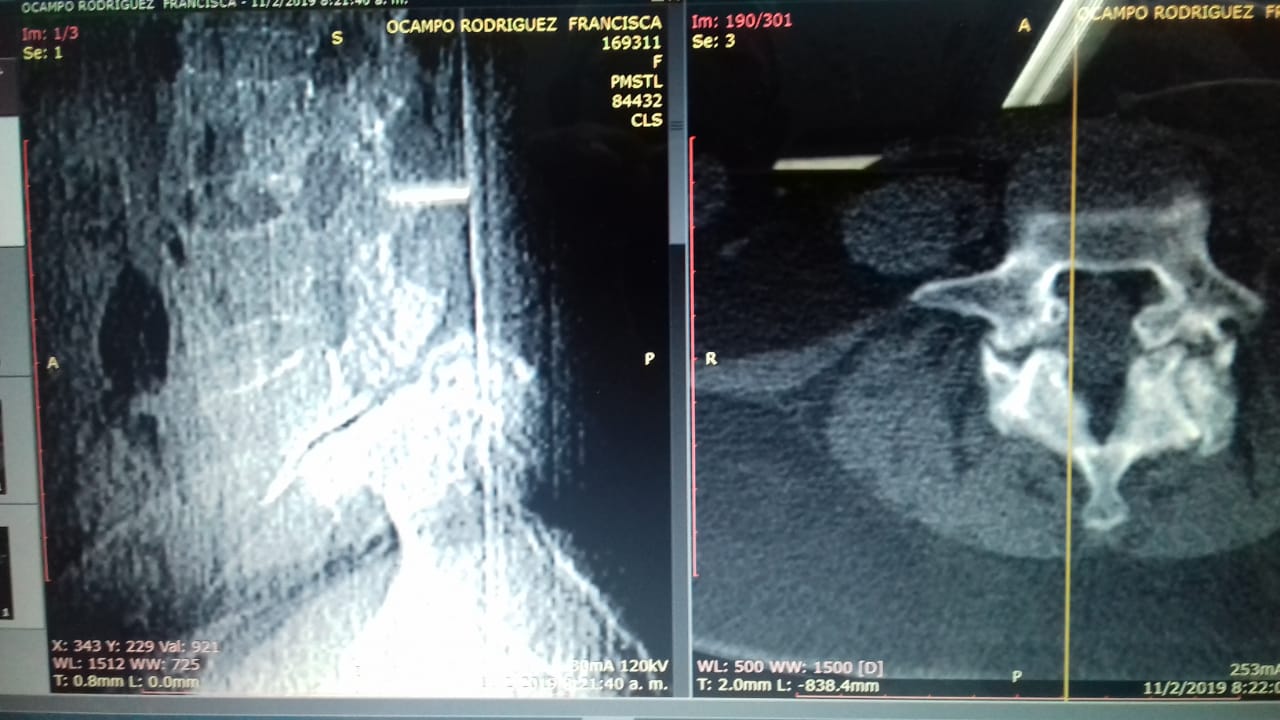

Fem. 60 años. Listesis L5S1 Dolos lumbar. Incapacidad Adormecimiento Pos quirúrgico sin evento. Sin Daño neurológico Seguimiento

Fem. 60 años. Listesis L5S1 Dolos lumbar. Incapacidad, Adormecimiento Pos quirúrgico sin evento. Sin Daño neurológico Seguimiento Dr, Manuel Orozco Ortopedista Centro De Diagnóstico Por Imágenes Linda Vista